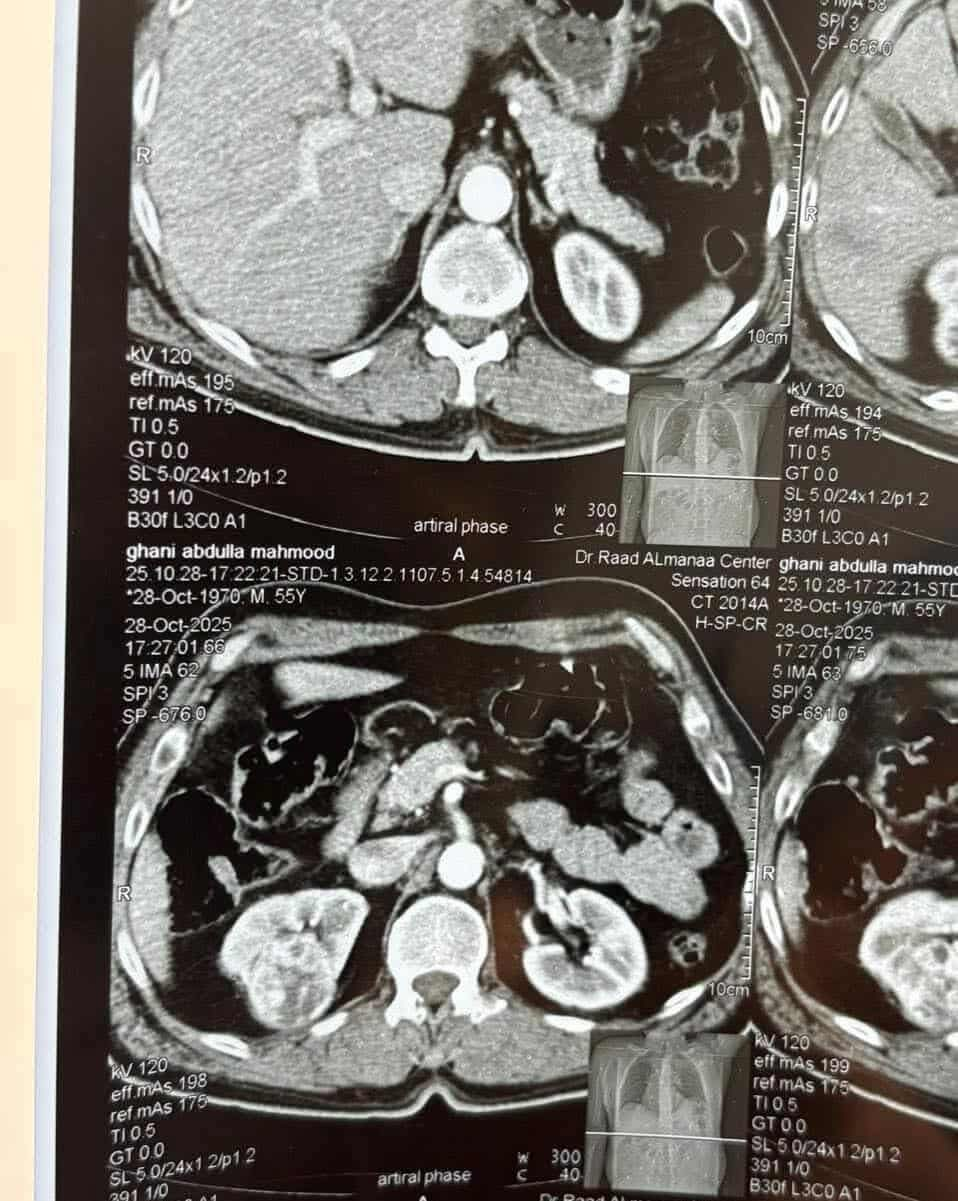

تمكّن فريق طبي متخصص بجراحة الكلى والمسالك البولية في مستشفى تكريت التعليمي التابع لدائرة صحة صلاح الدين من إجراء عملية نوعية ناجحة لمريض يبلغ من العمر 55 عامًا كان يعاني من ورم في الكلية اليمنى.

وبينت إدارة المستشفى إن الفريق الجراحي أجرى رفعًا جزئيًا للكلية، تضمن استئصال الورم مع جزء من الأنسجة المحيطة به مع الحفاظ على الكلية، واستغرقت العملية ساعتين متتاليتين، مؤكدة أن العملية تكللت بالنجاح.